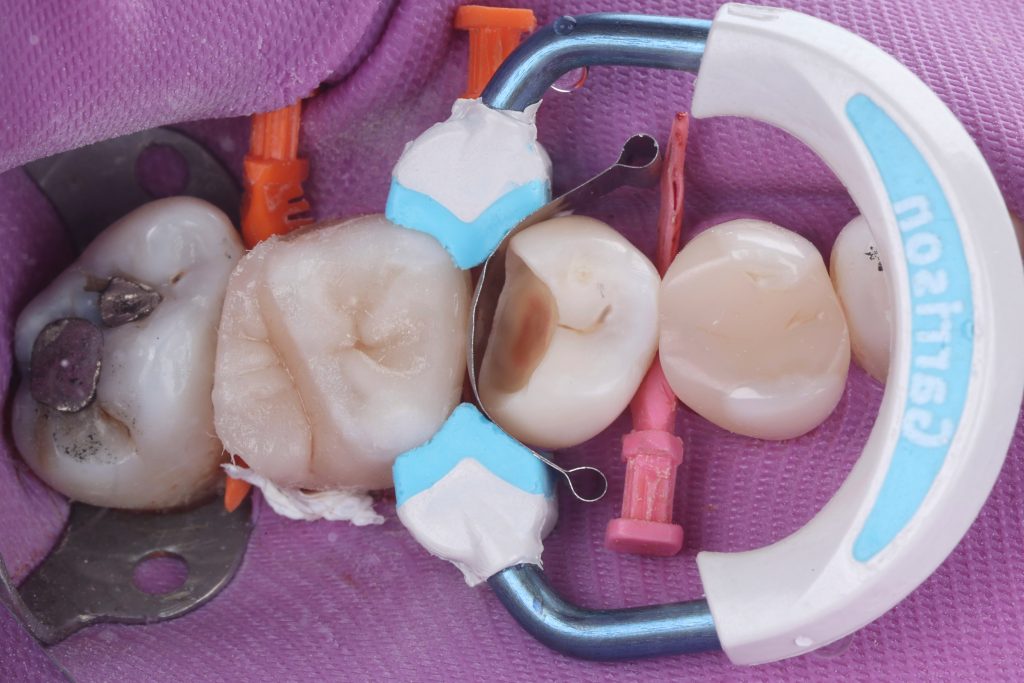

then composite modeling occlusally (cusp by cusp technique) to obtain esthetic & functional anatomy and avoid high spots ( take a reference from sound tooth structure of the same tooth or adjacent tooth )

Then some stains was applied.

The same steps was applied to the second premolar .

finishing and polishing was done by kerr Optidisc & shofu one gloss and eve twist till obtained highly polished restorations.